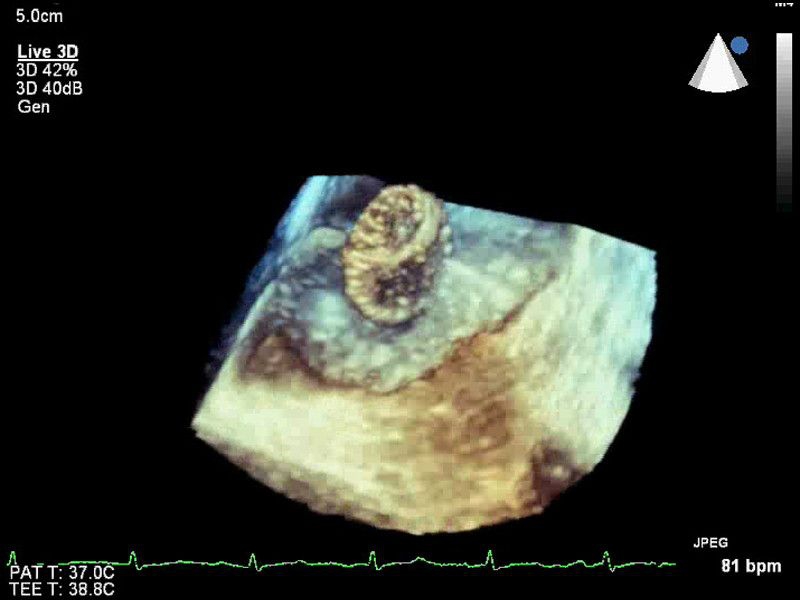

• Live 3D TEE: Эта функция позволяет проводить чреспищеводную эхокардиографию в режиме реального времени, что позволяет оценить механические сокращения сердца с точностью, необходимой для оценки результатов хирургического вмешательства.

• Live 3D Echo: Эта функция позволяет получать объемные 3D-изображения анатомии и механики сердца в режиме реального времени, расширяя возможности эхокардиографии.